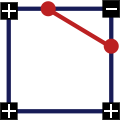

1. Три квадрата одного знака и один противоположного, движение контура происходит по диагонали:

2. Два квадрата одного знака и два противоположного, причем квадраты с одинаковым знаком находятся по одну сторону, движение контура идет вертикально или горизонтально: